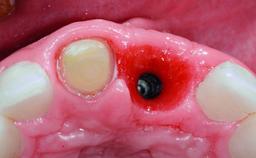

A 30-year-old patient presented at our clinic with a chief complaint of pain in her endodontically treated right maxillary central incisor (tooth 11) with a post-and-core and a fixed single crown. She had a very high lip line, a medium to thin soft-tissue phenotype, and a medium scalloped gingival contour. She also had high esthetic expectations because of her young age and beautiful smile. However, her expectations were realistic and she understood the risks of the treatment. At the initial clinical examination there was a slight mobility of tooth 11; no fistula was observed. The patient also had a single crown on the adjacent tooth 21. Both restorations were old and esthetically deficient. A digital periapical radiograph showed a very small periapical radiolucency, a thick intraradicular post, and no separation between root fragments.